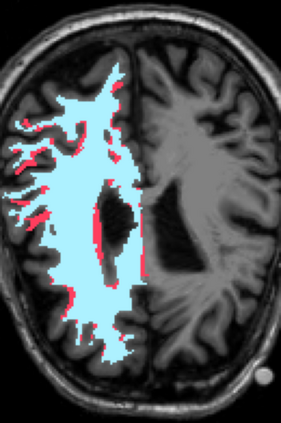

Deep neural networks for medical image reconstruction are traditionally trained using high-quality ground-truth images as training targets. Recent work onNoise2Noise (N2N) has shown the potential of using multiple noisy measurements of the same object as an alternative to having a ground truth. However, existing N2N-based methods cannot exploit information from various motion states, limiting their ability to learn on moving objects. This paper addresses this issue by proposing a novel motion-compensated deep image reconstruction (MoDIR) method that can use information from several unregistered and noisy measurements for training. MoDIR deals with object motion by including a deep registration module jointly trained with the deep reconstruction network without any ground-truth supervision. We validate MoDIR on both simulated and experimentally collected magnetic resonance imaging (MRI) data and show that it significantly improves imaging quality.